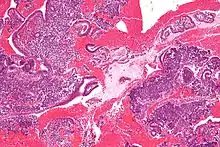

Histology of the most superficial layer of the endometrium, consisting of a simple columnar epithelium. H&E stain

The endometrium consists of a single layer of columnar epithelium plus the stroma on which it rests. The stroma is a layer of connective tissue that varies in thickness according to hormonal influences. In the uterus, simple tubular glands reach from the endometrial surface through to the base of the stroma, which also carries a rich blood supply provided by the spiral arteries. In women of reproductive age, two layers of endometrium can be distinguished. These two layers occur only in the endometrium lining the cavity of the uterus, and not in the lining of the fallopian tubes.[4][5]

• The functional layer is adjacent to the uterine cavity. This layer is built up after the end of menstruation during the first part of the previous menstrual cycle. Proliferation is induced by estrogen (follicular phase of menstrual cycle), and later changes in this layer are engendered by progesterone from the corpus luteum (luteal phase). It is adapted to provide an optimum environment for the implantation and growth of the embryo. This layer is completely shed during menstruation.

• The basal layer, adjacent to the myometrium and below the functional layer, is not shed at any time during the menstrual cycle. It contains stem cells that regenerate the functional layer,[1] which develops on top of it.